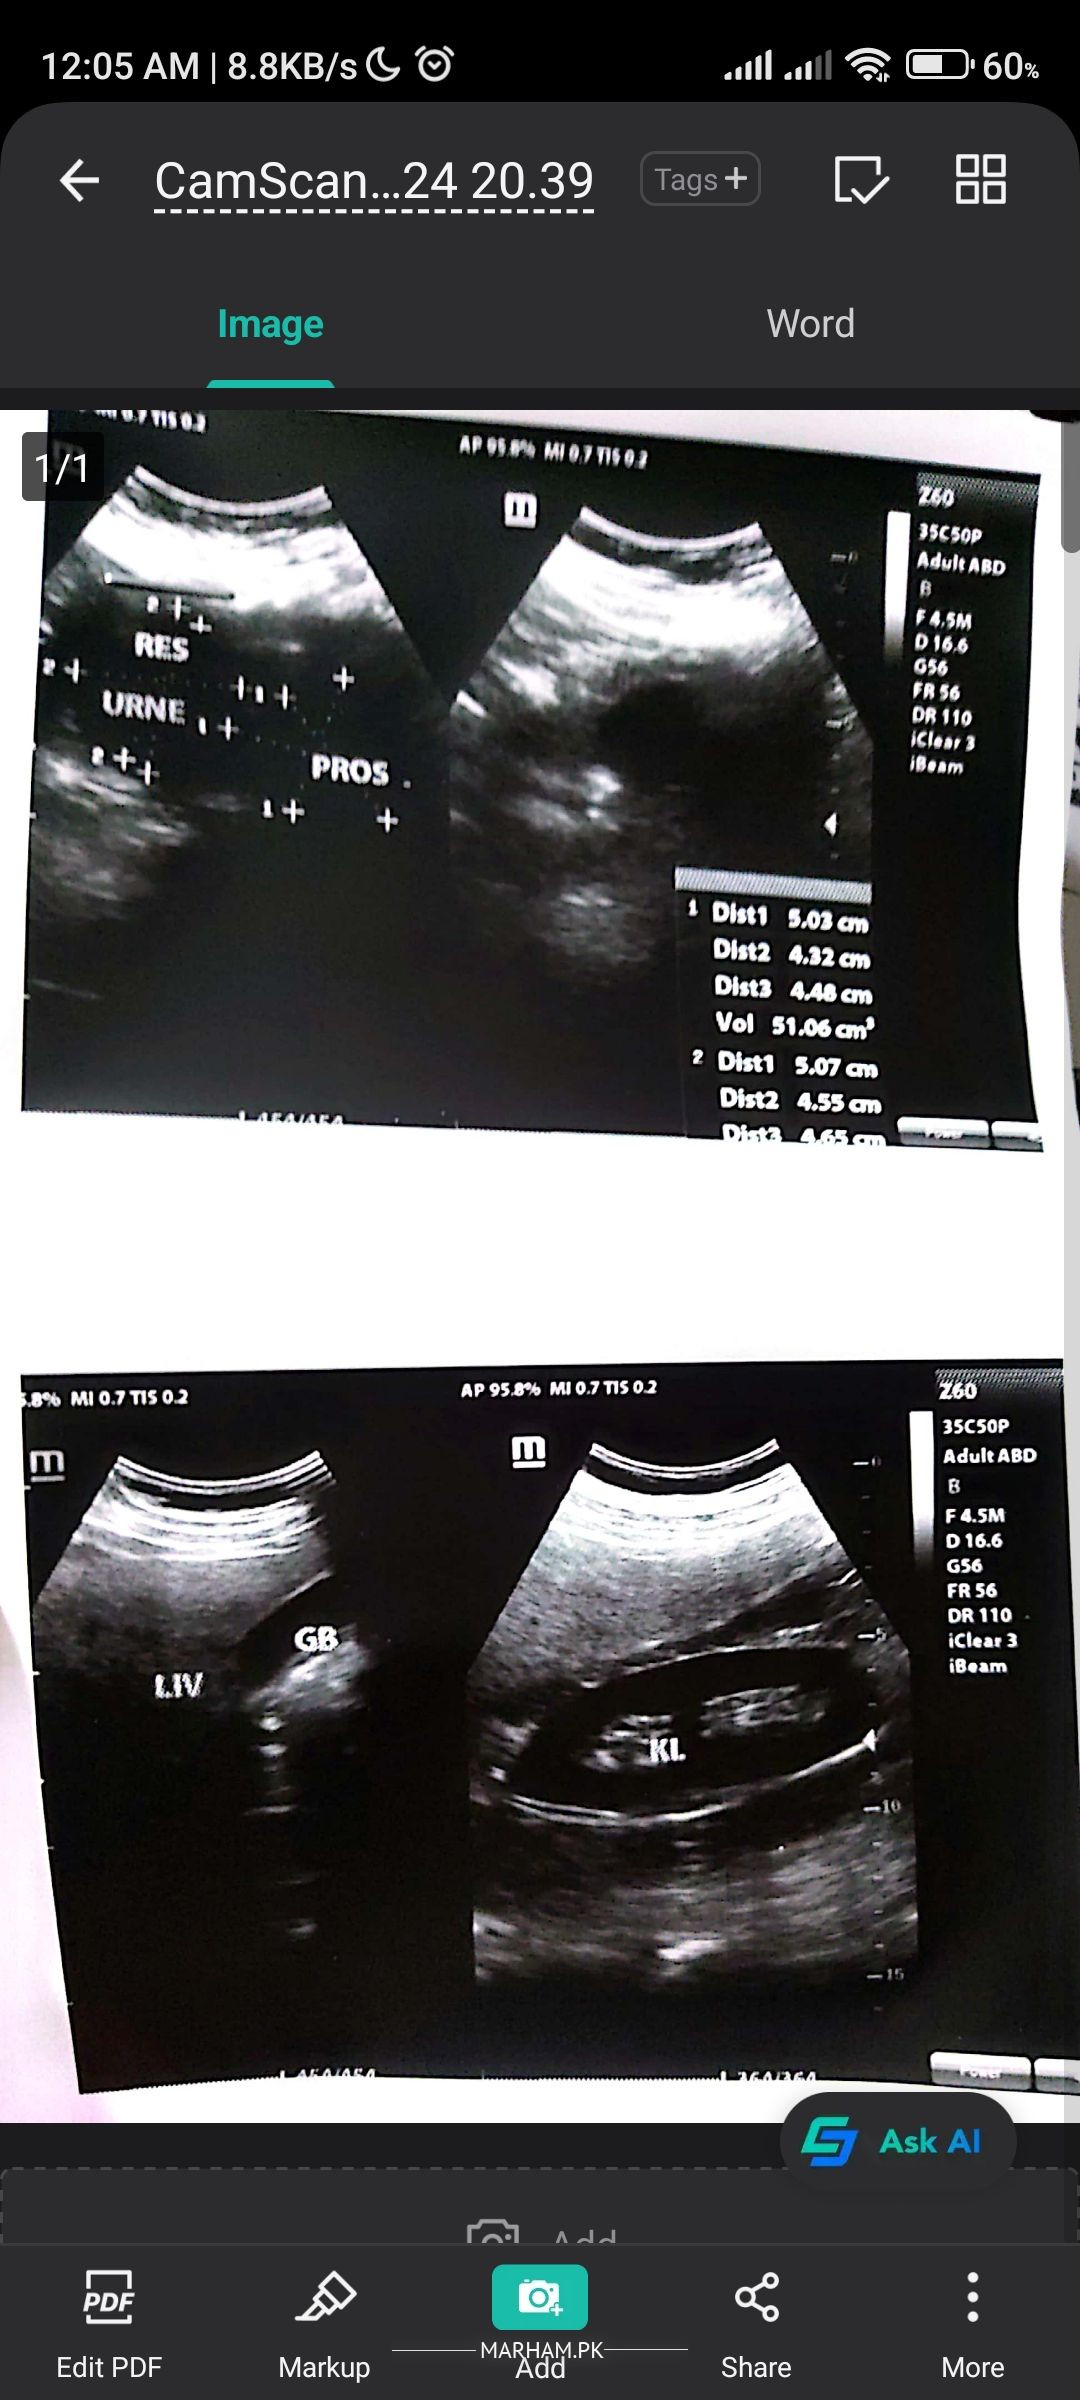

Information to be shared with the doctor.. 1 : The enlarged prostate was not available in the last scan which was 2 years old,

doc, yes this is post ultrasound, please the urinary bladdar note, 50ml is present after discharge.please suggest further

scan report is attached

please get an ultra sound for post micturition residual urine volume. that shall determine if he needs surgery.